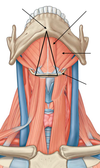

Identify the fascial layers surrounding the 4 facial compartments:

1st compartment: area surrounded by investing layer

2nd compartment: area surrounded by pre-vertebral layer

3rd compartment (visceral compartment): area surrounded by pre-tracheal layer

4th compartment: area surrounded by carotid sheath

Neck: Investing Layer of Deep Fascia

name the 2 superior attachments:

external occipital protuberance

superior nuchal line

Neck: Investing Layer of Deep Fascia

name the 4 inferior attachments:

scapular spine

acromion

clavicle

manubrium

Neck: Investing Layer of Deep Fascia

name the 2 posterior attachments:

ligamentum nuchae

spinous process of C7 vertebra

Neck: Investing Layer of Deep Fascia

name the 2 lateral attachments:

mastoid process

zygomatic arch

Neck: Investing Layer of Deep Fascia

(facts)

- splits to enclose sternocleidomastoid and trapezius

- surrounds infrahyoid muscles anteriorly

- forms the roof of the posterior triangle of neck

- goes from base of skull to superior thorax

- forms fibrous capsule of parotid gland

- is pierced by blood vessels (external + anterior jugular vv.) and nerves (lesser occipital, great auricular, transverse cervical, supraclavicular nn., and all branches of cervical plexus)